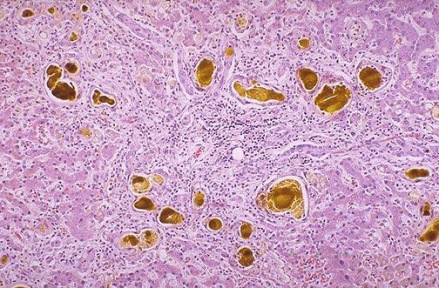

肝脏小胆管内可见黄绿色球状物,其为胆红素